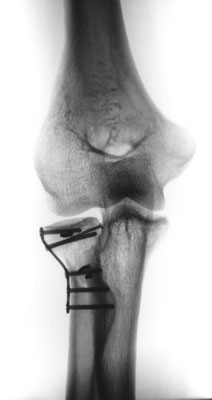

Radiusköpfchenbruch/Speichenköpfchenbruch

Einfache, sog. „Meißelbrüche“ des Speichenköpfchens können durch Minischrauben sehr stabil fixiert werden. Komplizierte Brüche müssen event. mit Miniplättchen verschraubt werden.

Bei ausgedehnter Zertrümmerung des Radiusköpfchens kann dieses mit Miniplättchen rekonstruiert werden oder sogar vollständig entfernt werden, ohne das die Funktion des Ellenbogens stark beeinträchtigt wird.

Häufiger kommt es allerdings zu zusätzlichen Bandverletzungen, insbesondere wenn der Ellenbogen luxiert war. In diesem Fall muss das Radiusköpfchen unbedingt erhalten werden, oder durch eine Radiusköpfchenprothese ersetzt werden. Durch die Wiederherstellung der knöchernen Führung wird die Stabilität des Ellenbogengelenkes wieder hergestellt. Zusätzlich wird der Bandapparat während der Operation genäht.